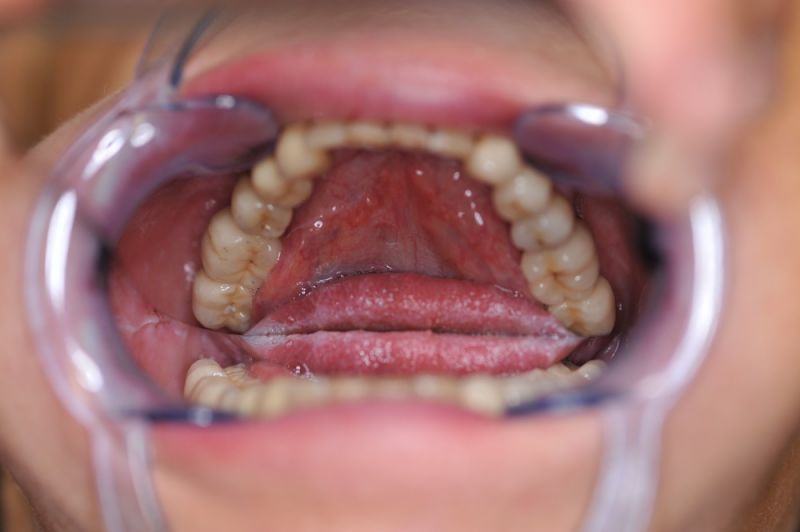

Schwierigster Fall aller Zeiten, praktisch beschwerdefrei. Patientin glücklich!

Wir übrigens auch!

Und wir haben es hinbekommen! Die Patientin hat heute zum Ausdruck gebracht, dass sie das selbst nicht für möglich gehalten hätte.

Alle 3 Monate Recall! Das ist jetzt Pflicht für diese Patientin und zwar so lange, so lange sie mit dieser Arbeit durch die Gegend laufen möchte! Und eiserne Disziplin bei der Mundhygiene!